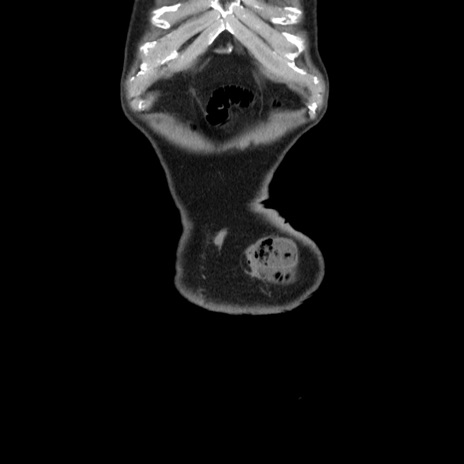

横断像

【症例】80歳代男性

【主訴】左側腹部痛、嘔吐

【現病歴】本日早朝より左腹部に痛みあり。昼頃嘔吐認めたため、救急要請。

【既往歴】直腸癌(Mile手術)、胆摘

【身体所見】意識清明、BT 35.9℃、BP 221/93mmHg、SpO2 97%(RA) 、腹部:左ストーマ周囲に限局性の腹部膨隆あり。 膨隆部自発痛・圧痛あり・軟。

【データ】WBC 7700、CRP 0.09